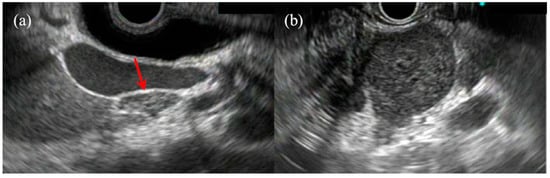

- Kim, G.H.; Park, D.Y.; Kim, S.; Kim, D.H.; Kim, D.H.; Choi, C.W.; Heo, J.; Song, G.A. Is it possible to differentiate gastric GISTs from gastric leiomyomas by EUS? World J. Gastroenterol. 2009, 15, 3376–3381. [Google Scholar] [CrossRef] [PubMed]